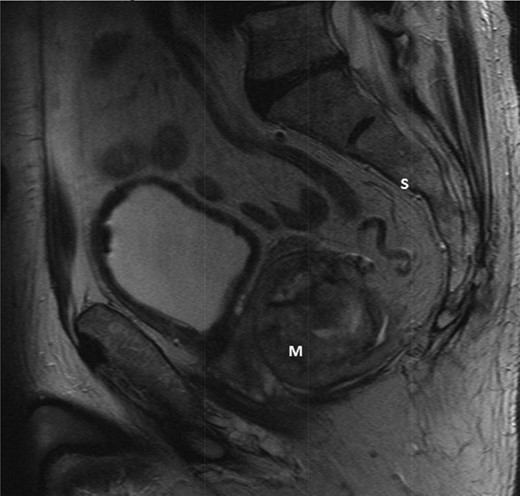

An elderly man in his seventies presented to the Urology department with two episodes of acute urinary retention. There were no rectal symptoms and rectal examination revealed an enlarged prostate. He underwent a laser transurethral resection of prostate during which a large palpable pelvic mass was noted. The subsequent urgent MR pelvis revealed a large tumour in the mesorectum arising from the anterior rectum 10 × 8.5 cm (Figs 1 and 2). A transrectal ultrasound and biopsy were performed; histology revealed a spindle cell tumour, with positive immunostains for CD117 and DOG1 with 5 mitoses per 50 high power fields. This was confirmed to be a locally advanced high-risk GIST.

T2-weighted sagittal image demonstrating a large mass (m) anterior to the sacrum (S) and posterior to the bladder.

T2-weighted sagittal images after 3 months of imatinib mesylate therapy. The mass has shown a significant reduction in size (Mass = m, Sacrum = s).